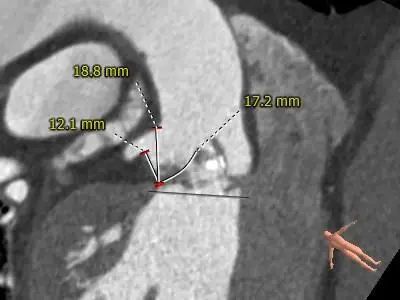

LEFT CORONARY

RIGHT CORONARY

LCA&LEAFLET

RCA&LEAFLET

冠脉开口高度可,左冠切线角度测量瓣叶略长于LCA开口下缘到根部距离。